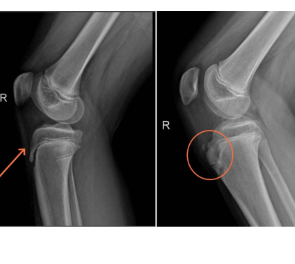

左图为正常的青少年胫骨结节,右图为病变的青少年胫骨结节,可见明显凸起。

李宝军介绍,大腿前侧的股四头肌通过髌腱,连接在小腿胫骨上端的一个凸起处,这个凸起就叫“胫骨结节”。当孩子反复跑、跳、踢球时,股四头肌会猛烈收缩,通过髌腱反复牵拉尚未完全长结实的胫骨结节,会导致这块软骨发生损伤、炎症,甚至撕裂,身体为了修复它,会过度增生骨组织,从而形成一个永久的、摸起来硬硬的隆起。这也就是为什么一开始没检查就判断他是这个病的原因,体征是比较典型的。

第三,患处会轻微肿胀或隆起。如果反复发作,这个地方会形成一个坚硬、不移动的骨性隆起,不痛,但会一直存在。疼痛仅限于胫骨结节,膝关节内部(关节腔)通常没有积水或肿胀,这有助于和膝关节内部损伤(如半月板损伤)鉴别。